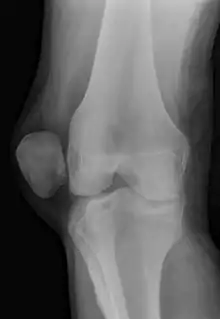

![]() | |

| X-ray showing a patellar dislocation, with the patella out to the side. | |